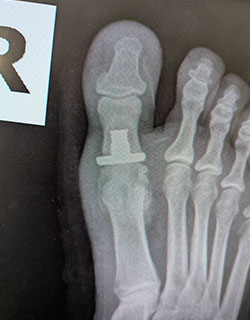

Hallux rigidus (severe arthritis of the big toe joint) causing painful, limited motion of the joint and requiring removal of the arthritic bone and partial joint replacement (hemi-arthroplasty) to allow full range of motion and return to weight bearing.

Before SurgeryBefore

After SurgeryAfter